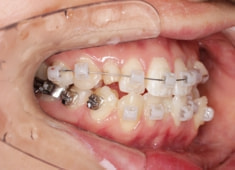

治療中